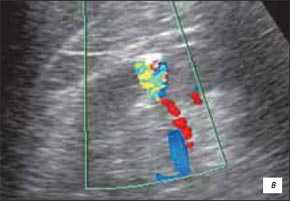

5. УЗИ при бертиниевых колоннах почки:

• Исследование 8 режиме серой шкалы:

о Нормальный контур почки

о Обычно изоэхогенно по отношению к корковому веществу

о Цветовое и энергетическое допплеровское картирование позволяет визуализировать поток, идентичный корковому веществу

о Разделение центральных эхосигналов

(Слева) УЗИ, продольная плоскость сканирования: гипоэхогенное «объемное образование» в центре, которое выступает в почечную лоханку.

(Справа) КТ с контрастированием, аксиальная проекция: у этого же пациента установлено, что «объемное образование» — это нормальное корковое вещество почки, которое инвагинирует в почечную лоханку между чашечками верхнего полюса и меж полюсной областью почки. Обратите внимание на нормальный внешний контур почки. Бертиниевы колонны чаще всего выявляют с одной стороны и слева, как в данном случае: в 18% случаев они могут быть двусторонними.